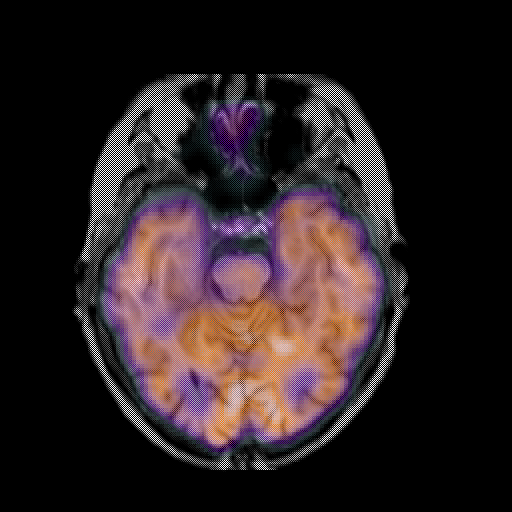

overlay: Slice 19

Slice 19

MRCBFCBF with

T1PDT2T1PDT2